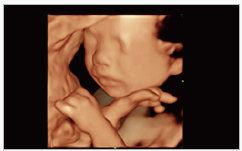

Mindray Ultrasound Consona N9

صور متعلقة